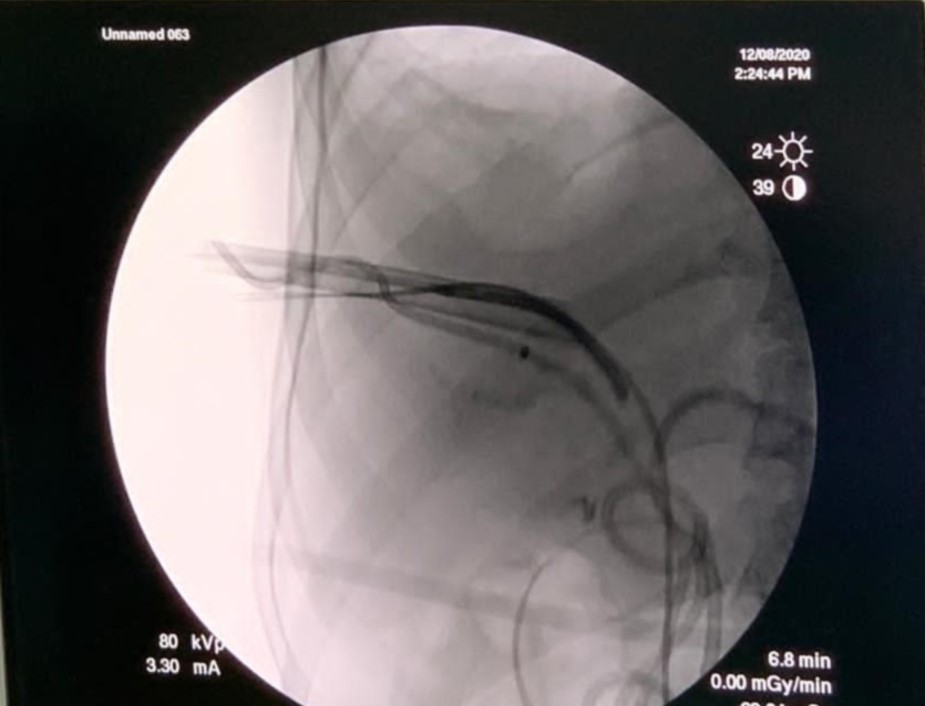

حيث قام الفريق بإزالة الحصوات الموجودة داخل الكبد (Intrahepatic biliary ducts) عن طريق الاشعة التداخلية بتقنية "التقابل" عن طريق الجلد دون الحاجة للتدخل الجراحي والدخول إلى قنوات الكبد بعد اجراء عمليات توسيع على ثلاثة مراحل تحت التخدير الموضعي في أول مرتين وإزالة الحصوات من القنوات المرارية خارج الكبد(Extrahepatic biliary ducts) باستخدام مناظير القنوات المرارية عن طريق الفم (ERCP) دون الحاجة نهائياً للجوء الى الجراحة التقليدية او الجراحة بالمنظار.